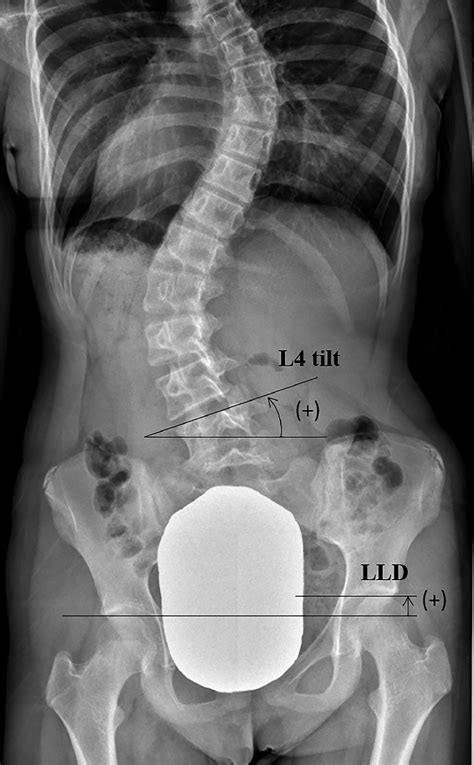

Alright, let’s break down what typically goes into a scoliosis radiology program . It’s not a one-size-fits-all deal, but most programs will focus on a few key areas to ensure practitioners are well-equipped. First off, imaging modalities are central. This means getting hands-on (or at least deeply familiar) with X-rays, specifically full-spine standing X-rays, which are the gold standard for initial assessment. We’re talking about understanding radiation dose, patient positioning for optimal views (like AP - anterior-posterior, and lateral), and the specific markers used to measure curves, like the Cobb angle. Beyond X-rays, depending on the program and the suspected cause, you might delve into CT scans for detailed bone structure and MRI for soft tissues, nerves, and spinal cord evaluation. The interpretation of images is another massive chunk. This involves learning to identify the type of scoliosis – idiopathic (most common, cause unknown), congenital (born with it), or neuromuscular (due to nerve or muscle conditions). Radiologists need to meticulously measure curve magnitudes, look for rotational changes, and assess vertebral body abnormalities. They’re trained to spot red flags that might suggest conditions like spinal tumors or infections, which can mimic scoliosis. Radiation safety is non-negotiable, guys. Protocols for minimizing radiation exposure to patients, especially children who are more sensitive, are heavily emphasized. This includes using the lowest effective dose settings and appropriate shielding. Finally, patient interaction and communication are often included. While radiologists are primarily behind the scenes, understanding how to communicate findings to referring physicians, and sometimes directly to patients or their families, is a vital skill. This often involves clear explanations of what the images show and the implications for treatment. Some advanced programs might even touch upon newer technologies like EOS imaging systems, which provide low-dose, 3D imaging of the entire skeletal structure. It’s a comprehensive education aimed at producing experts who can provide the clearest possible picture of a patient’s spinal health. The continuous evolution of imaging technology means these programs are also constantly updated to include the latest advancements, ensuring that the practitioners are always at the forefront of diagnostic capabilities. This dedication to comprehensive training ensures that every scan contributes meaningfully to patient care.

So, why the fuss about specialized training, you ask? Why can’t any radiologist just look at a spine X-ray? Well, the spine is a complex beast, and scoliosis imaging requires a level of detail and understanding that goes beyond a general radiological assessment. Specialized training in scoliosis radiology ensures that the professionals viewing these images possess a deep understanding of spinal anatomy, biomechanics, and the various pathologies that can lead to spinal curvature. For instance, recognizing the subtle differences between a simple idiopathic curve and one caused by a congenital anomaly requires specific knowledge. The measurement of curves, most notably the Cobb angle, needs to be precise. Small variations in measurement technique can lead to significant differences in perceived curve progression, impacting treatment decisions like whether surgery is needed. Radiologists trained in scoliosis protocols know exactly how to take these measurements consistently and accurately. Furthermore, scoliosis often affects developing children and adolescents. This means radiologists must be acutely aware of growth plates, skeletal maturation (using tools like the Risser sign), and how these factors influence curve progression and treatment outcomes. They need to consider the long-term implications of imaging findings on a growing body. Radiation dose optimization is another critical aspect where specialized training shines. Children are more vulnerable to the effects of radiation, so minimizing exposure while obtaining diagnostic-quality images is paramount. Specialized programs teach techniques and protocols specifically designed for pediatric patients, ensuring they receive the safest possible imaging. Think about it: a standard chest X-ray protocol is vastly different from a scoliosis series. The technologists and radiologists in these programs are trained to administer the right amount of radiation, just enough to see what they need to see, and no more. This careful balance is a hallmark of expert care. Without this specialized knowledge, there’s a risk of misinterpretation, inaccurate measurements, delayed diagnosis, or even unnecessary radiation exposure. It’s about ensuring that every imaging study provides the maximum benefit with the minimum risk, ultimately contributing to better patient outcomes and a more confident approach to managing scoliosis. The expertise gained here is not just about reading scans; it’s about understanding the patient’s entire clinical picture and how the imaging fits into the broader management strategy. This holistic view is what differentiates a general radiologist from a scoliosis imaging specialist.

Let’s talk tech, guys! The world of scoliosis radiology is constantly evolving, bringing forth innovative technologies and refined techniques to get the clearest possible view of the spine. The bedrock, as we’ve mentioned, is still the X-ray . However, even within X-ray technology, there have been significant advancements. We’re seeing the increased use of EOS imaging systems . These are pretty cool because they use a low-dose biplanar X-ray system to create simultaneous anterior-posterior and lateral images of the entire body in a standing position. The real kicker? The radiation dose is significantly lower compared to traditional full-spine X-rays, which is a huge win for pediatric patients who often require frequent monitoring. EOS also provides 3D modeling capabilities, giving an even more comprehensive view of spinal alignment and posture. Digital radiography (DR) has largely replaced older film-based systems. DR offers better image quality, faster acquisition times, and crucially, allows for digital manipulation of contrast and brightness, which can help in visualizing subtle details without re-exposing the patient. Computed Tomography (CT) scans are typically used when more detailed information about bone structure is needed, perhaps to assess the bony elements involved in congenital scoliosis or to get a precise view before surgical planning. While CT provides excellent bony detail, it does involve higher radiation doses than standard X-rays, so its use is carefully considered. Magnetic Resonance Imaging (MRI) is the go-to for evaluating the spinal cord, nerve roots, and surrounding soft tissues. If a radiologist suspects that the scoliosis is secondary to an underlying neurological issue, such as a tethered spinal cord, tumor, or syrinx, an MRI is essential. It provides unparalleled soft-tissue contrast without using ionizing radiation. Fluoroscopy , which provides real-time X-ray imaging, might be used during certain interventional procedures related to scoliosis management or diagnosis, but it’s less common for routine diagnostic imaging of the curve itself due to radiation concerns. Lastly, image processing and measurement software are integral. Advanced software allows for automated or semi-automated measurement of the Cobb angle, vertebral rotation, and other key parameters. This improves consistency and accuracy in tracking curve progression over time. The integration of these technologies within specialized programs ensures that practitioners are adept at selecting the most appropriate imaging tool for each patient’s unique situation, optimizing diagnostic yield while prioritizing patient safety. It’s a sophisticated toolkit that helps unravel the complexities of the spine.